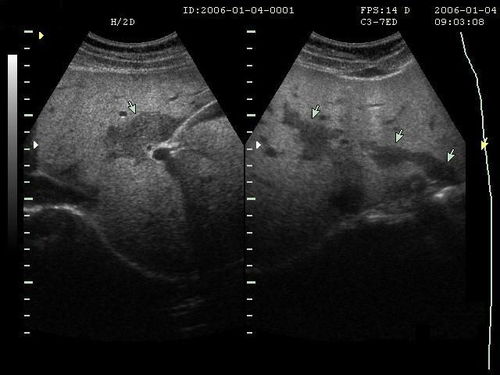

病情分析:您好:乙肝B超檢查安全,快速,無損傷,所以這成為很多乙肝患者復查要做的項目.意見建議:首先,乙肝B超檢查前要空腹,并做好檢查前的腸道準備.腹腔的肝,膽,胰的B超檢查應該不要吃東西,避免胃腸食物和氣體對超聲波的干擾,保證膽囊及膽管等器官內(nèi)有足夠的膽汁充盈,從而確保診斷的準確性.乙肝B超檢查通常安排在每天上午.乙肝患者最好在做乙肝B超檢查前3日禁食牛奶,豆制品,糖類等易于發(fā)酵產(chǎn)氣食物,檢查前1天晚吃清淡少渣飲食,食后禁食一夜,注意休息,檢查當天需早上需要空腹禁食,禁水.另外有些乙肝患者雖然沒有吃早餐,但在凌晨兩三時吃過東西,同樣會影響乙肝B超檢查效果.其次,乙肝B超檢查中一定要按照醫(yī)生要求,積極配合.在乙肝B超檢查中,醫(yī)生常常會要求乙肝患者一直“吸氣”,此時應該按照醫(yī)生的指令進行呼吸運動,這樣才能有助于更好地觀察.此時“吸氣”可以促使肺部氣體充滿,這樣會使得膈肌向下移動,這樣乙肝B超檢查結(jié)果才能更好地顯示肝臟,膽囊.。